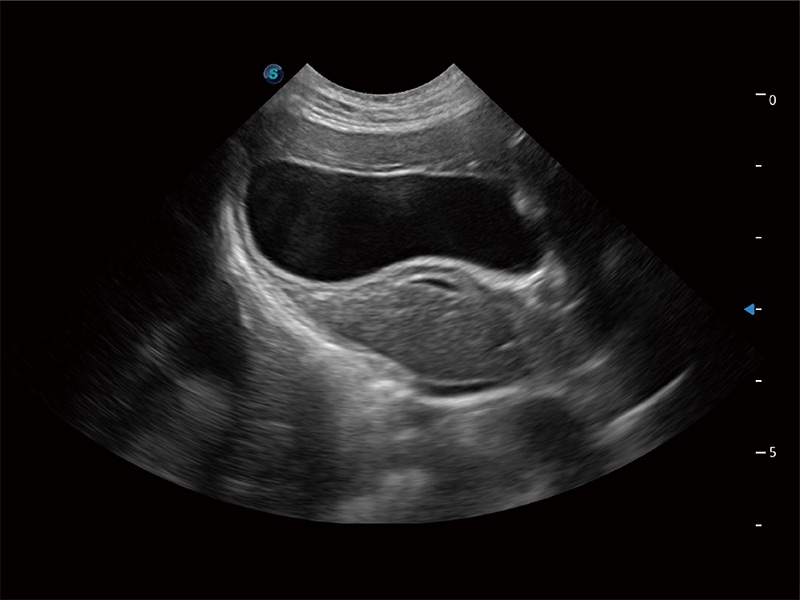

一键自动识别膀胱壁及自动测量膀胱容积,不受膀胱形状和大小的限制,帮助医生快速精准获得测量的数据。